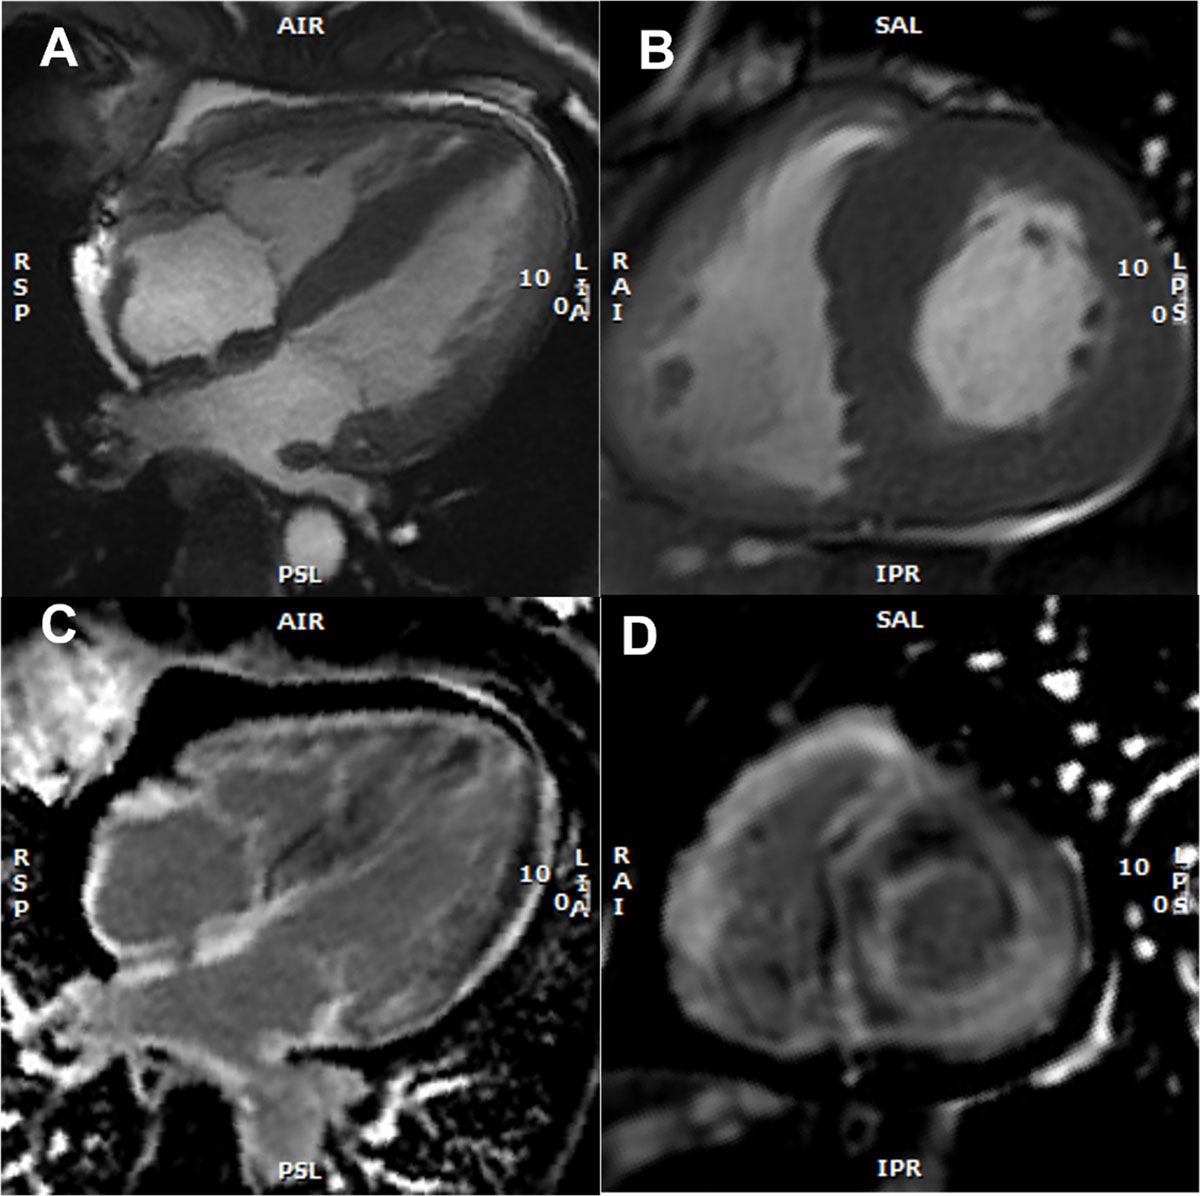

Figure 5

Cardiac magnetic resonance imaging findings with representative examples. (A) Cine: four-chamber view – SSFP (steady-state free precession) acquisition, depicting asymmetric left ventricular (LV) hypertrophy, inter-atrial septum thickening, and mild pericardial effusion (B) Short axis view – SSFP, asymmetric LV hypertrophy (C) Late gadolinium enhancement (LGE) at the 4-chamber view with subendocardial LGE at the left ventricle, atrial Wall, and inter-atrial septum (D) Short axis view, showing subendocardial and subepicardial LGE at the left ventricle and also at the right ventricle. (Images courtesy of Lusíadas Hospital, Lisboa, Portugal).